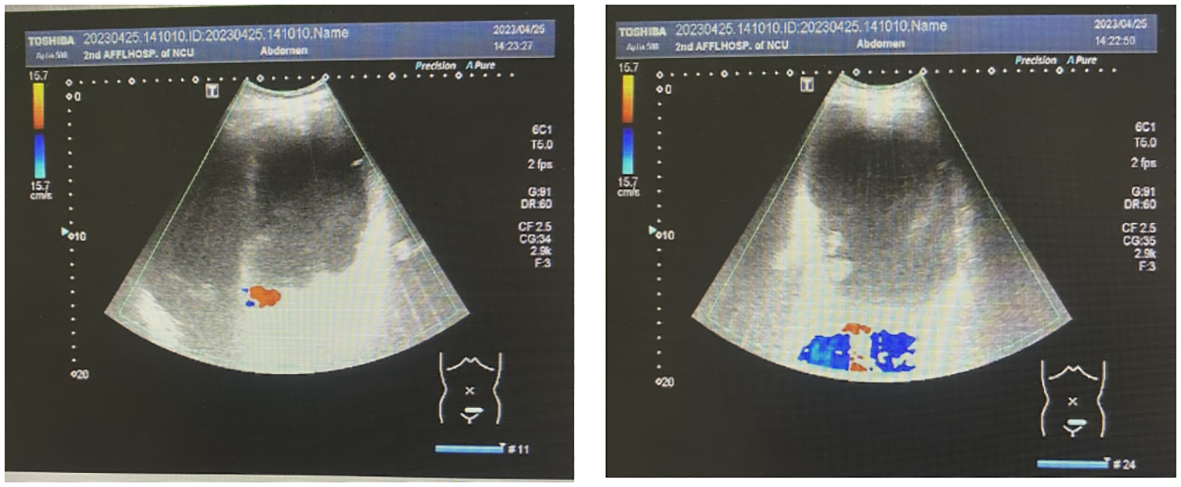

Abdominal color ultrasonography showed the presence of a large cystic mass in the abdominal pelvis and a polyp in the gallbladder. The spleen was enlarged (Figure 2). Color ultrasonography of the urinary system showed mild hydronephrosis of the right kidney and widening of the upper segment of the right ureter, with obstruction of the middle and lower segments, not due to the compression by the large huge mass. No obvious abnormalities were found in the left kidney, left ureter, and bladder.

Figure 2

Abdominal color ultrasonography scans.